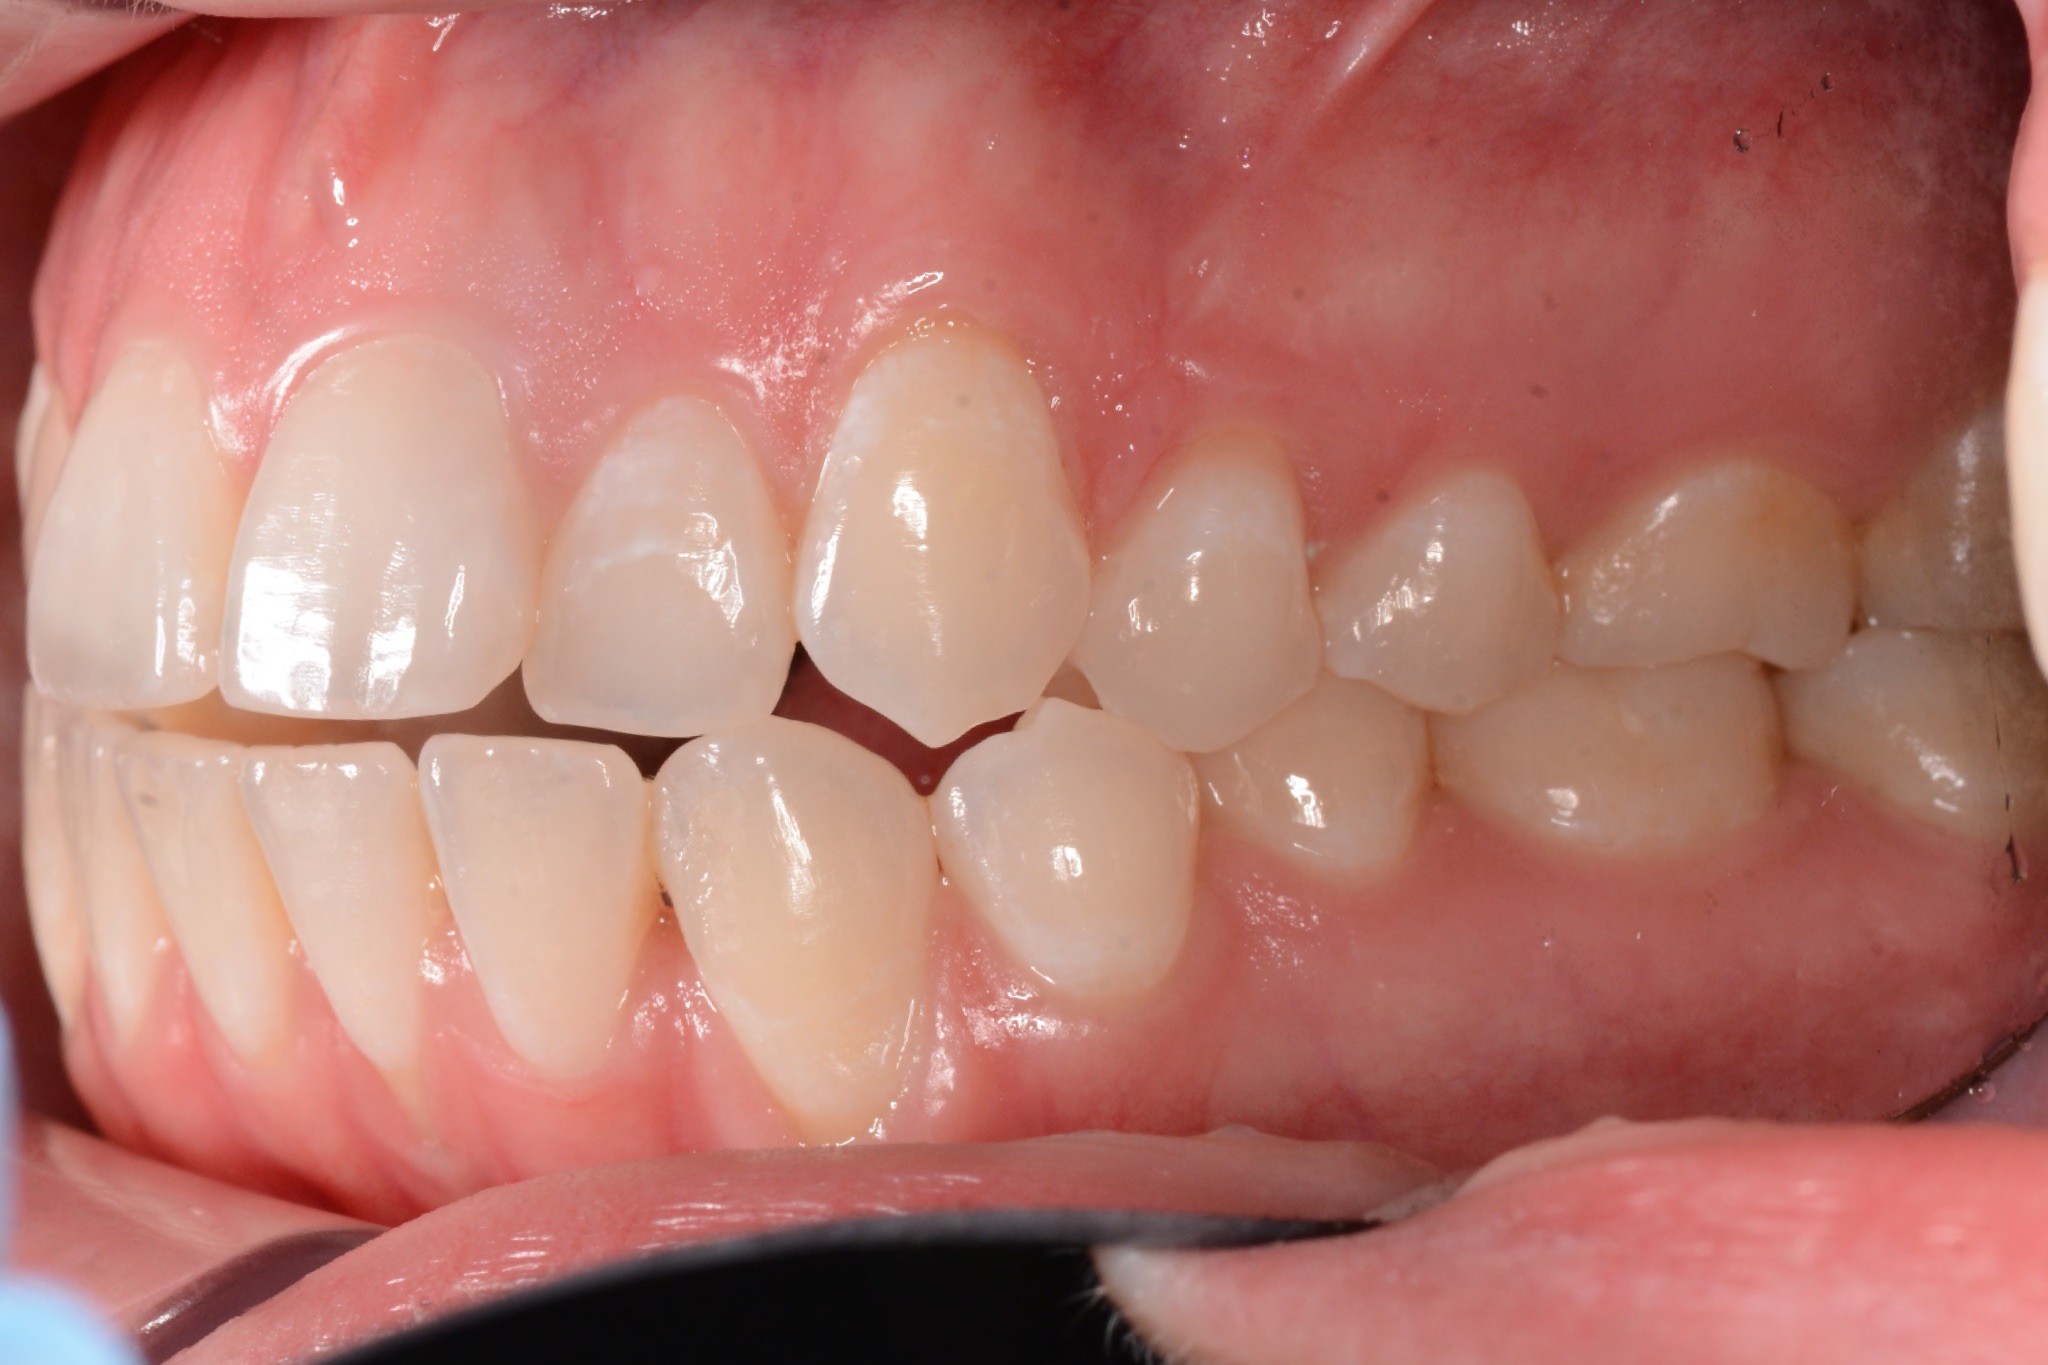

Initial treatment

INTRAORAL